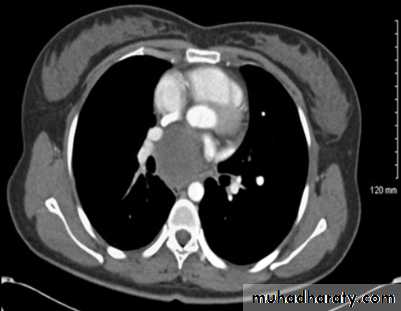

Aortic aneurysm : Dilatation of the ascending aorta may be due to aneurysm

formation or secondary to aortic regurgitation, aortic stenosis or systemic hypertension.

Computed tomography with intravenous contrast enhancement, magnetic resonance angiography (MRA) and/or echocardiography are very useful when aortic aneurysms are assessed .

Aortic aneurysm